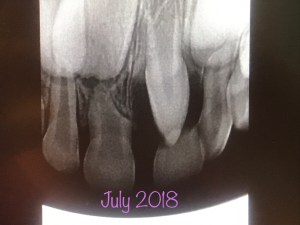

And I guess it’s the gift that keeps on giving through the generations–now my daughter has a “unicorn tooth” a supernumerary (extra) tooth right in the middle of her two front adult teeth so she has an exiting dental future too! At least unicorns 🦄 are totally in now and she’s excited about the huge prize she’s going to get when the unicorn 🦄 tooth fairy 🧚🏻♀️ collects her tooth at the unicorn dentists office (oral surgeon) after her nap! Oh, the stories I’ve concocted with this one, just so that my daughter has a positive experience with the dentist and does not develop a fear! So that’s happening in the beginning of the New Year, but before that I’ve got my own dental emergency…. again!

So, if my teeth have not experienced enough dental damnation, recently, I had a small cavity that turned into an abscessed tooth and infection in jaw. A dentist did half a root canal so now….